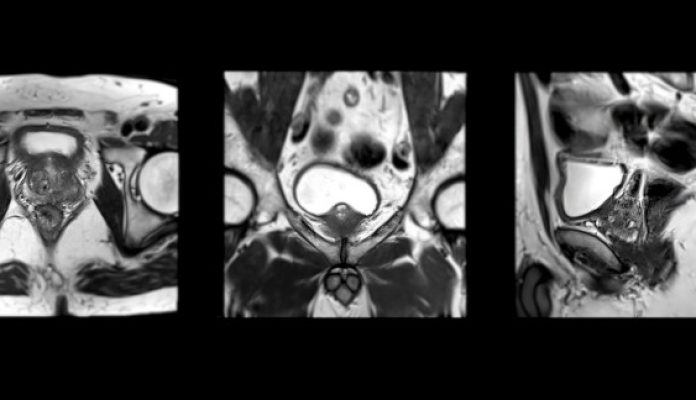

UroLift and Radiotherapy

Evaluating the Role of UroLift in Radiotherapy Planning: Retrospective Analysis of the Largest Known Series of Pre-Radiotherapy Urolifts.